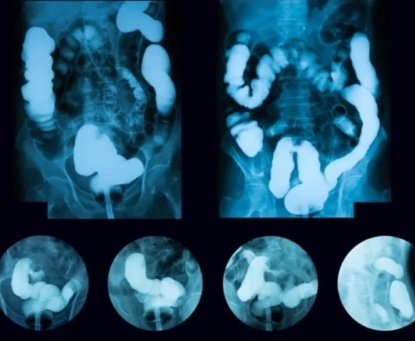

GIST có thể phát hiện thông qua các xét nghiệm hình ảnh nào?

Các xét nghiệm hình ảnh là một phần quan trọng trong việc phát hiện và chẩn đoán u mô đệm đường tiêu hóa (GIST).